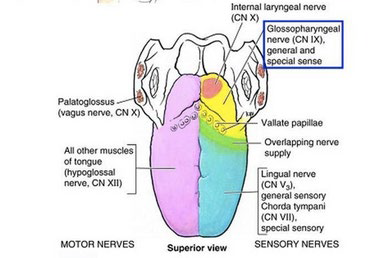

Nerve

運動

感覺

- 根部 taste/ general sense

- 後 taste/ general sense

- 前

- Taste: Chorda tympanic

- General sense: Lingual n

Muscle

Extrinsic muscles

Motor:CN XII

移動舌頭

- Genioglossus(makes bulk of the tongue)

- Hyoglossus

- Styloglossus

Motor:CN X (Pharyngeal plexus)

- Palatoglossus

Intrinsic muscles

Motor:CN XII

改變舌頭形狀